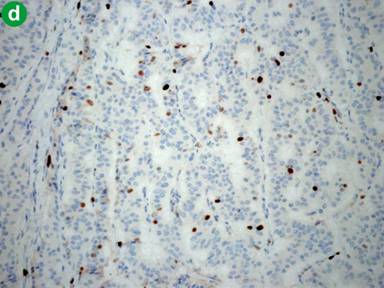

Macroscopically, the pancreatic mass weighted 23 g and measured 23x16x11 mm. The mass was oval-shaped, well-demarcated, soft and pinkish in color. Cut-surface showed tan soft tissue. Microscopically, the uniform intermediate-sized tumor cells were organized in solid trabeculae or nests separated by fibrovascular stroma (Figure 2). The cells had centrally located oval-shaped nuclei, stippled (salt-and-pepper) chromatin and scant finely granular eosinophilic cytoplasm. No evidence of mitosis was identified. Furthermore, there was no evidence of vascular or perineural invasion. Surgical resection margins were tumor-free. Immunohistochemically, tumor cells stained positive for chromogranin A, synaptophysin, insulin and Ki-67 (6%) (Figure 3). Tumor cells stained negative for somatostatin. Based on the clinical, laboratory, imaging, histopathological and immunohistochemical studies, a final diagnosis of benign insulinoma neuroendocrine tumor, World Health Organization (WHO) grade 2, was established.

Figure 3. Immunohistochemical examination of the resected pancreatic mass (magnification power, 40x). a. Tumor cells stained positive for chromogranin A. b. Tumor cells stained positive for synaptophysin. c. Tumor cells stained positive for insulin. d. Tumor cells stained positive for Ki-67 (6%). |